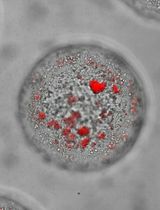

用于抗转移治疗研究的三维肝脏类球乳腺癌微转移模型

A Model of Breast Cancer Micrometastasis in a Three-Dimensional (3D) Liver Spheroid for Testing an Antimetastatic Therapy

Even though the survival and proliferation stages of cancer cells that have newly settled at a metastatic site are the rate-limiting stages and the most promising targets for drugs, there is a lack of models of the earliest stage of metastasis formation. A method for modeling breast cancer liver metastasis is described here: a stage of transition of a differentiated tumor cell into a cell actively proliferating in a three-dimensional (3D) liver spheroid. Opposite to existing heterocellular 3D models of metastases, the protocol allows modeling the initial stage of liver colonization by metastatic cells, the so-called “micrometastases.” The method includes obtaining a line of fluorescent tumor cells, fluorescence-activated sorting of differentiated cells, preparing a single-cell suspension of liver cells, forming a liver spheroid in an agarose mold, inducing the tumor cell dedifferentiation and proliferation using IL-6, and intravital microscopy of spheroids, with subsequent processing and analysis of fluorescent images in the ImageJ software. The performance of the proposed model was demonstrated using microRNA therapeutics. The ability of a combination of microRNAs to suppress the transition of micrometastasis to macrometastasis in the 3D liver spheroid was confirmed by an immunofluorescent assay of spheroid sections and transcriptome analysis.